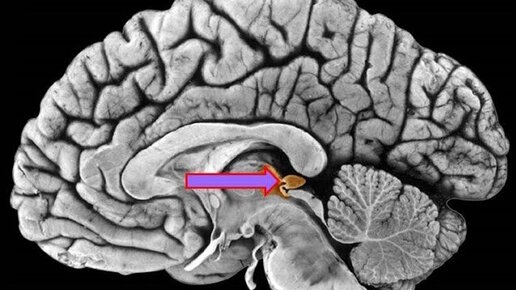

С.В. Савельев - Эпифиз /15.09.2016/